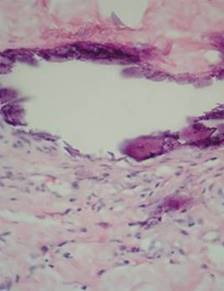

También, según Wilmer y Magro,22 la patogenia de la calcifilaxis se puede dividir en dos etapas. En la etapa uno se desarrolla la lesión vascular con sensibilidad inducida por la PTH, vitamina D o hipercalcemia. En la segunda etapa se presenta la isquemia secundaria a lesiones vasculares calcificadas asociadas con fibrosis y trombosis vascular (Figuras 1 y 2).

Figura 1: Biopsia de piel en tinción de hematoxilina-eosina (40X). Calcificación de capa media de arteriolas de dermis reticular.

Figura 2: Biopsia de piel en tinción hematoxilina-eosina (100X). Hiperplasia de la capa muscular por depósito de hidroxiapatita que produce oclusión del vaso y necrosis isquémica.